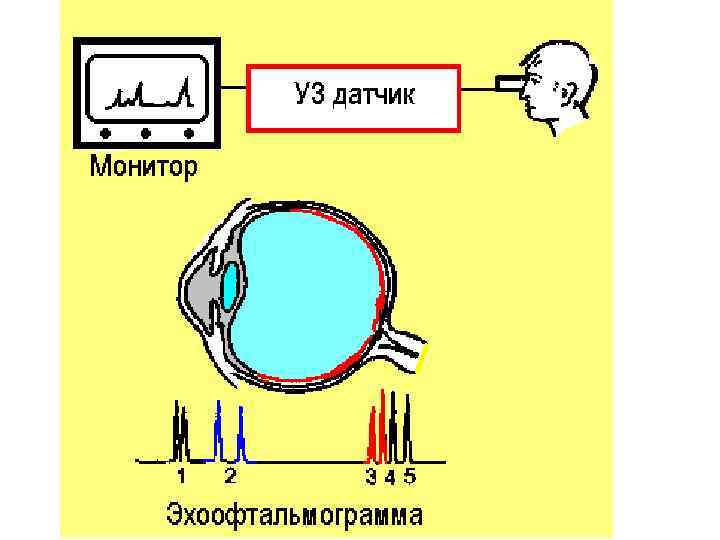

• Ультразвуковое исследование глаза

• Ультразвуковое исследование глаза